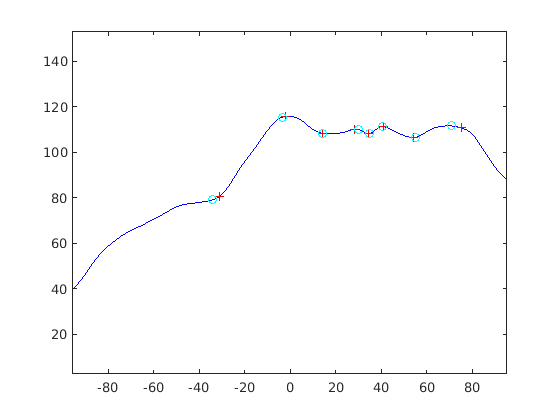

We find that , with values close to zero indicating locally flat regions, positive values indicating convexities, such as the pronasale (nose tip), and negative values indicating concavities, such as the nasion. Effectively this is a discrete approximation to finding the area within the facial profile that intersects with a disc of some predefined scale. The discrete sampling gives a high frequency quantisation noise on the signal and so we filter this with a 10th order low pass Butterworth filter.

The operator is very easily adapted to multiple scales, with smaller scales being straightforward subsamples of the disc points at larger scales. In this case, we reapply Eqn. 3 to the subsample and, as with the larger scale, apply a low pass filter. A useful property of the operator, in contrast to a standard curvature operator, is that its scale is easily tuned to the size of the features that one is interested in: we use a 20mm disc radius for most profile landmarks (nasion, pronasale, subnasale, chin concavity and pognion), except those around the lips (upper lip, lower lips, centre of lips), where we use the smallest scale, 5mm. Fig. 15 illustrates the disc operator’s output at four scales to illustrate its behaviour. For 5 of 8 facial profile landmarks, the strongest output is (usually) the largest scale. For the remaining three, the strongest output is the smallest scale.

|

|

The landmarking algorithm employed finds the nearest strong local extrema of the appropriate sign and at the appropriate scale. Our initial thought was to use a search from the largest to the smallest scale for all landmarks, We implemented this, but it often failed around the lip region, perhaps because the lower lip and upper lip localisations in the initial sparse model fit are very close to each other. Instead, we refine the pognion (chin), subnasale, pronasale (nose tip) and nasion at the largest operator scale. We then consider upper, centre and lower lips simultaneously by looking for a strong M-shaped disc operator signature at the smallest scale (5mm, cyan, in Fig. 15), between the subnasale and pognion. Finally, we find the chin cleft location as the strongest minimum between the lower lip and pognion.